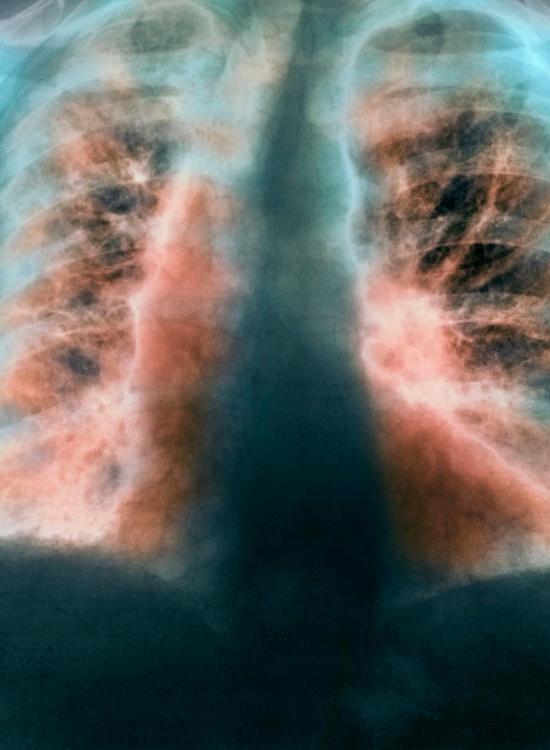

L’infezione da coronavirus potrebbe infatti determinare conseguenze a lungo termine sulla funzionalità respiratoria e talvolta comprometterla in modo irreversibile, soprattutto nei pazienti usciti dalla terapia intensiva.

Tanto che nei pazienti più gravi colpiti da covid-19, il trenta per cento dei guariti avrà problemi respiratori permanenti di fibrosi polmonare.

Nei pazienti più gravi colpiti dall’infezione, dunque, il trenta per cento dei guariti avrà problemi respiratori permanenti da fibrosi polmonare: “In molti pazienti Covid-19 che sono stati ricoverati o intubati osserviamo dopo la dimissione difficoltà respiratorie che potrebbero protrarsi per molti mesi dopo la risoluzione della infezione e i dati raccolti in passato sui pazienti con sars mostrano che i sopravvissuti a sei mesi di distanza avevano ancora anomalie polmonari ben visibili alle radiografie toraciche e alterazioni restrittive della funzionalità”.

“Ma, soprattutto – precisa Richeldi – il trenta per centop dei pazienti guariti mostrava segni diffusi di fibrosi polmonare, cioè grosse cicatrici sul polmone con una compromissione respiratoria irreversibile: in pratica potevano sorgere problemi respiratori anche dopo una semplice passeggiata”.